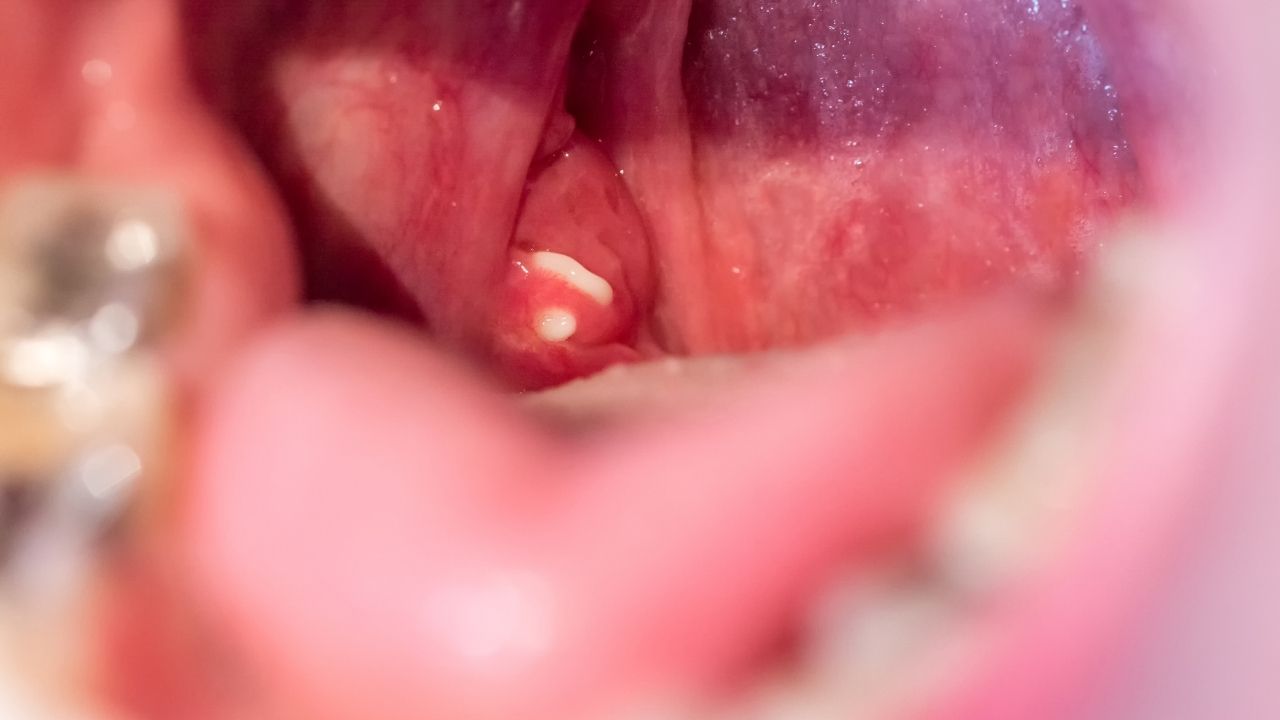

જો શરીરમાં કોઈપણ પ્રકારનો ચેપ હોય તો મોંમાંથી લાળ ટપકવાની સમસ્યા શરૂ થાય છે. આનું સૌથી મોટું કારણ ગળું, સાઇનસ ચેપ અથવા કાકડા હોઈ શકે છે.